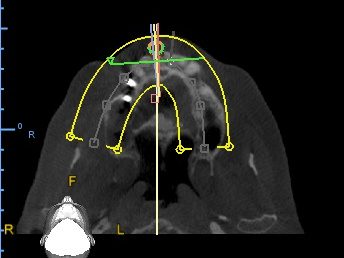

Implant Planning Case 1